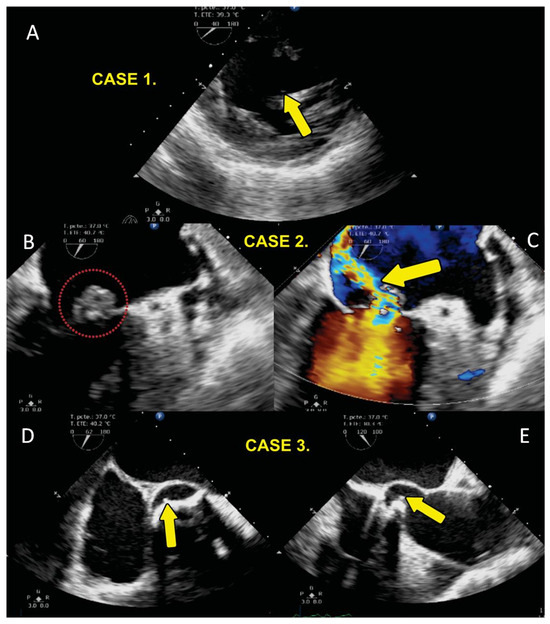

| 1 | 55 | F | 20 | 2009 diagnosis of Arteritis de Takayasu plus bicuspid aortic valve SAH 1999 AVR by severe AoI (Medtronic Hall). | Endocarditis in 2016. Univalve prosthetic valve with pannus and abscess with tissue destruction at level of interventricular septum with bacterial growth with Staphylococcus aureus and epidermidis. Surgery AVR and implantation of dual-chamber pacemaker by complete BAV; she had ischemic stroke and left hemiparesis with evolution with reduced heart failure LVEF 25% and died in 2017, one year after surgery. | yes |

| 2 | 78 | F | 24 | DAoI and stenosis AoI, trivalve aortic valve. In March 2019, she received intervention with TAVI. Portico 25 mm plus Boston Scientific DDD pacemaker, tachycardia–bradycardia syndrome. Comorbidities: smoking, systemic arterial hypertension and dyslipidemia. | In 2009, the patient was diagnosed with DAoI with predominant stenosis, which did not require surgery at that time. Four years later, the patient presented tachycardia–bradycardia syndrome and a Boston Scientific DDD permanent pacemaker was placed. In 2019, ten years after the initial DAoI diagnosis, the stenosis worsened and TAVI was considered for AVR. Five days later, the patient presented mitral–aortic endocarditis, which required an explant transcatheter implanted with a prosthetic aortic valve plus resection of the ascending aorta plus MVR with an Edwards Perimount 21 biological prosthesis plus Bentall and Bono surgery with a Woven Dacron 24 tube. In April 2019, the patient underwent TAVI and developed endocarditis with vegetation in the aortic valve. Mitral–aortic junction abscess plus aortitis aortic wall abscess. Valve crop Enterobacter cloacae, Klebsiella oxytoca. She was treated with aortic valve explanation surgery, ascending aorta resection. Bentall and Bo, MVR Edwards Peri mount. Mitroaortic command surgery. As of 2024, she is alive with LVEF 40%. | no |

| 3 | 67 | M | 30 | In 2019, DAoI and AoI severe bicuspid aortic valve, LV systolic and diastolic dysfunction LVEF 20%, smoking. | In 2020, native valve endocarditis with mobile vegetation of left non-coronary valve plus ascending aortic aneurysm, surgery AVR Medtronic Hall with bacterial growth with Streptococcus viridans. In 2024, normal functioning of prosthesis, LVEF 57%. | no |